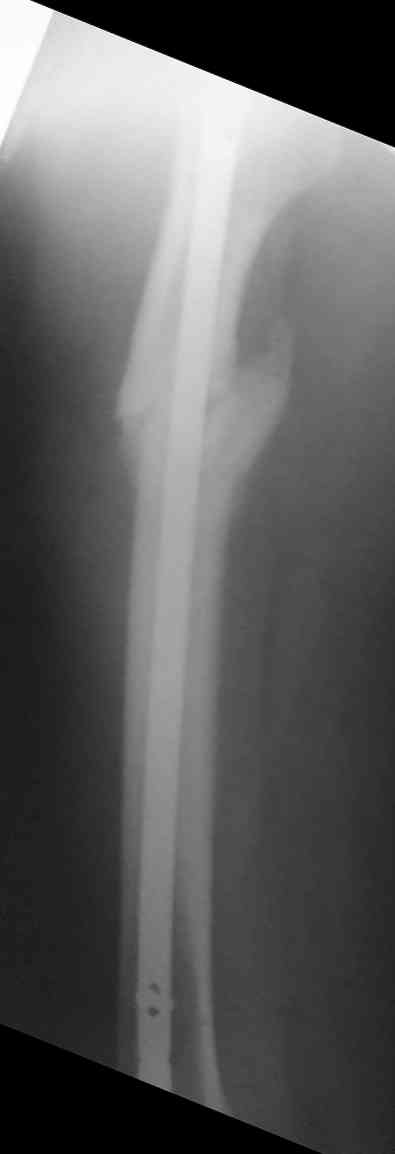

> денамизация - февраль 2006. ( 3 и 4 снимки) на сегодняшний день (снимок 5) беспокоит боли в тбс...

Судя по уровню перелома, винты в шейку избыточны, подойдет и диафизарный гвоздь. Все, что нужно, это тиски и труба. Загнуть сразу ниже отверстий градусов на 8-10, и вся недолга. Последние годы у нас это рутинная практика. Предызогнутые еще с завода гвозди неудобны тем, что они уже правый-левый.

Вот несколько. С тисками и трубой на днях сделаем.

> Вот несколько. С тисками и трубой на днях сделаем.

Саша, последний штифт, пожалуй, перегнули?

Там заход сделан как для прямого штифта, не через вертел.